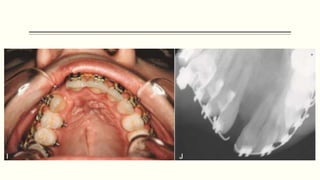

Alveolar Cleft Grafts

 The alveolar cleft defect is usually not corrected in the original surgical correction of the

cleft lip or the cleft palate.

 Residual oro-nasal fistulae in this area, and the maxillary alveolus will not be continuous

because of the cleft.

 Because of this, five problems commonly occur:

1. Oral fluids escape into the nasal cavity

2. Nasal secretions drain into the oral cavity

3. Teeth erupt into the alveolar cleft

4. The alveolar segments collapse

5. If the cleft is large, speech is adversely affected.

Alveolar Cleft Grafts - Advantages

1. They unite the alveolar segments and help prevent collapse and constriction of the

dental arch.

2. Alveolar cleft bone grafts provide bone support for teeth adjacent to the cleft and for

those that will erupt into the area of the cleft.

3. Closure of the oronasal fistula.

4. Facilitates the use of dental prostheses by creating a more suitable supporting base.

5. The creation of a solid foundation for the lip and alar base of the nose.

 Timing of graft procedure; the patient is between ages 6 and 10 years, a major portion of

maxillary growth has occurred, and the alveolar cleft surgery should not adversely affect

the future growth of the maxilla.

 Surgical procedure.

 Intact mucoperiosteal flaps on each side must cover bone grafts placed into the alveolar

cleft.

 The bone placed into the alveolar cleft is usually obtained from the patient’s ilium or

cranium; however, some surgeons are using allogeneic bone (i.e., homologous bone from

another individual) and recently bone morphogenetic proteins (BMP)

 The grafts are made into a particulate consistency and are packed into the defect once

the nasal and palatal mucosa has been closed.

 The labial mucosa is then closed over the bone graft.